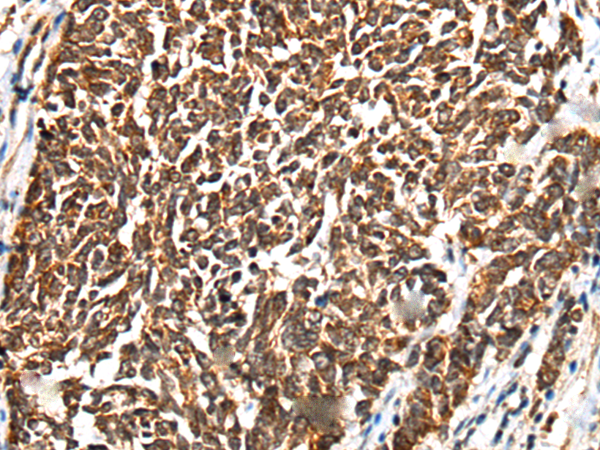

IHC positive control: |

Human lung cancer and human tonsil |